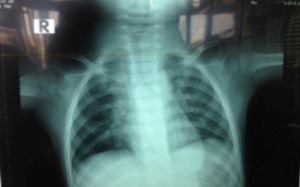

Đang ăn mãng cầu, cháu bé 11 tháng tuổi bất ngờ ho sặc sụa, khó thở, tím tái. Ngay sau đó, bé được đưa đến bệnh viện để cấp cứu.